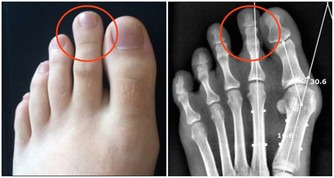

4. 小便頻次過低

排便的頻率與攝入水分的多少密切相關,當人處在脫水狀態時,排尿量和排尿的頻次必定會顯著減少。大家可以適當觀察一下自己每次排便相隔的時間,當間隔時間超過了平均數值時,很有可能是脫水所致。攝入充足的水分有助於加速新陳代謝,能幫人體盡快排出毒素。那麼脫水便意味著體內的有害物質無法被代謝,長時間淤積在體內便會損害相關器官和組織,甚至會誘發類似於腎結石之類的疾病。